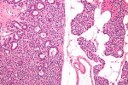

Figure 1, Figure 2, Figure 3, Figure 4, Figure 5, Figure 6, Figure 7, Figure 8

Figure 4.MEN1 syndrome demonstrating a parathyroid adenoma with encapsulation and glandular proliferation13.